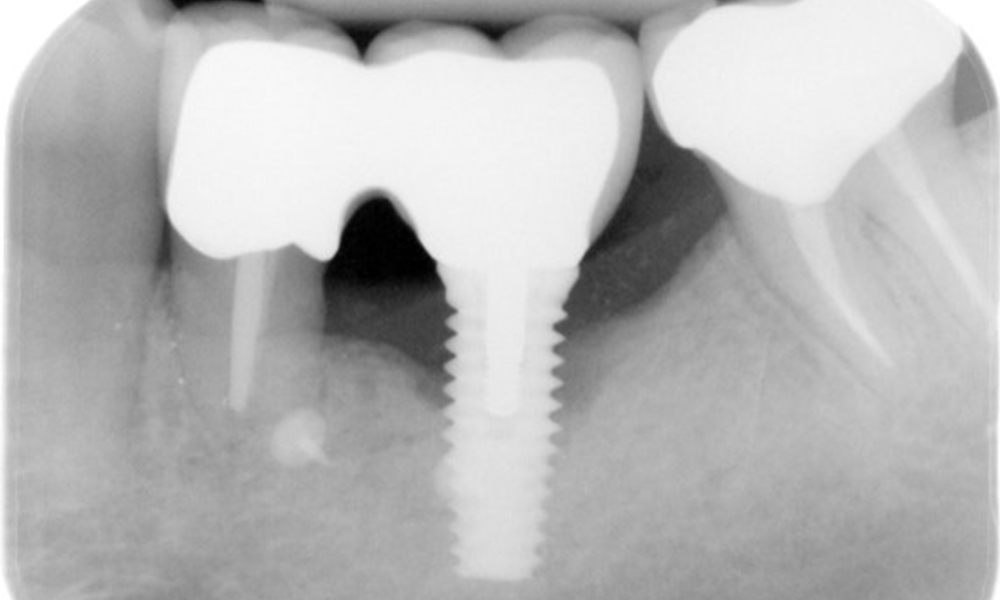

The patient has no particular risk factors with specific dental implications in his medical history. The key factor, therefore, is the requirement in terms of oral health. In this respect, there is evidence of a probing depth of 5 mm at the implant in the 3rd quadrant and, on the X-ray image, increased bone loss. The patient also has currently stable early periodontal disease and two active initial carious lesions.

The X-ray images show the progression of bone loss in the area of the implant in region 36: dental film from 11.02.2021 (left) and dental film from 18.01.2024 (right).